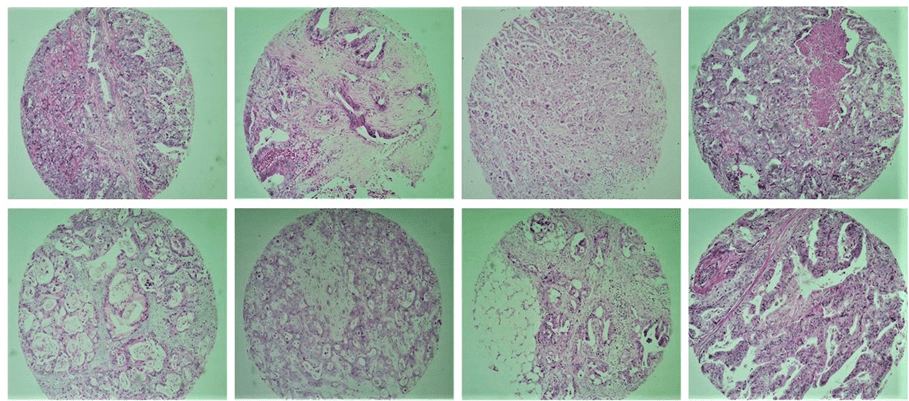

Tissue Microarray (TMA) Array ist eine Technik, die zuerst von Kononen et al. (1998) beschrieben wurde und ist ein großartiges Werkzeug für die Untersuchung pathologie. Es geht darum, eine angemessene Anzahl von Gewebeproben in einem einzigen Block zu gruppieren und so die Untersuchung der immunhistochemischen Expression molekularer Marker zu ermöglichen, mit großem Einsatz des Materials, Vorhandensein von interner Kontrolle sowie Zeit und Kosteneffizienz. Diese Technik ermöglicht auch die Standardisierung von Reaktionen, effiziente Repräsentativität durch die Verwendung verschiedener Bereiche des Tumors, Das Studium einer großen Anzahl von Proben gleichzeitig, einfache Interpretation und groß angelegte Forschung von prognostischen oder prädiktiven Faktoren von Krebs (Abbildung 1).

Abb. 1. Veranschaulicht einige Tumorgewebeproben, die in der Studie durch die TMA-Technik enthalten sind